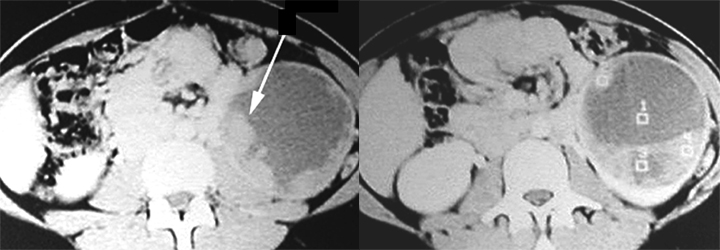

Renal Cell Carcinoma

- Arrow: Solid hypodense mass left kidney

- Arrowhead: Normal parenchymal enhancement

- Mass is cystic and solid.

- Tumor nodules are seen arising from the wall of the cyst pointed by long arrow.